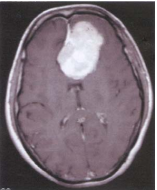

74 51 歲女性,主訴近半年來,頭痛、右下肢麻及無力,根據所附 MRI 圖(T1WI with Gd-DTPA),則 其診斷是:

(A) Glioblastoma multiforme(GBM) (B) Oligodendroglioma (C) Giant aneurysm (D) Meningioma